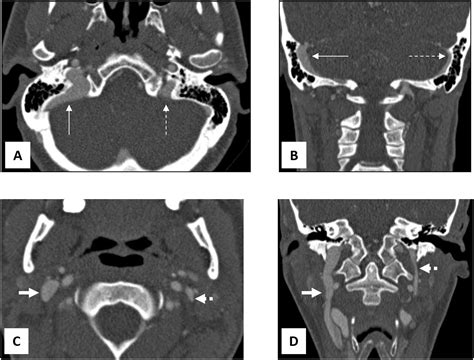

• Venous Sinus Stenosis: Narrowing of the venous sinuses—the large veins that drain blood from the brain—is a very common cause of pulsatile tinnitus.

• Dehiscence of the Superior Canal: A tiny hole in the bone covering the inner ear can make normal bodily sounds, including blood flow, seem significantly louder.

During your appointment, a specialist will likely perform a physical examination of your ears and neck. They may order imaging tests, such as an MRI, MRA (Magnetic Resonance Angiography), or CT scan, to visualize the blood vessels and structures near your ear. These imaging techniques are the "gold standard" for uncovering the precise pulsatile tinnitus causes that may be affecting you.